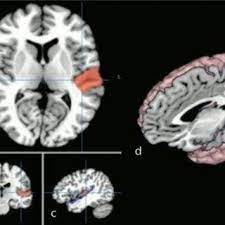

Here are two illustrations, without and with the context of the surrounding cortex:

The precise location of the primary region in humans is variable, however, as is the arrangement of heschl's gyri (some people have one of these gyri, while others have two or three). Localization of the primary auditory area in man. Brodmann area 41) is located along the upper bank of the superior temporal gyrus, within the lateral sulcus on two gyri known as heschl's gyri. Medical dictionary for the health professions and nursing © farlex 2012 want to thank tfd for its existence? It was subdivided into primary (a1) and secondary (a2), as well as and further association areas. The primary auditory cortex in humans is hidden within the lateral sulcus on a collection of gyri known as heschl's gyri (aka the transverse temporal gyri). Primary auditory cortex function the auditory area is a significant part of the hearing process. Temporal modulation, such as amplitude modulation (am), is a ubiquitous sound property used for a variety of functions such as, but not limited to, vocalization.

The modern divisions of the auditory cortex are the core (which includes primary auditory cortex, a1), the belt (secondary auditory cortex, a2), and the parabelt (tertiary auditory cortex, a3). Brodmann area 41) is located along the upper bank of the superior temporal gyrus, within the lateral sulcus on two gyri known as heschl's gyri. Brodmann area 41) is located along the upper bank of the superior temporal gyrus, within the lateral sulcus on two gyri known as heschl's gyri. Thus, it contains a precise tonotopic map. Although knowledge about macaque primary auditory cortex (a1) has grown in recent years, little is known about the transformations occurring in higher auditory cortical areas. The primary auditory cortex (fig. The region of the cerebral cortex that receives the auditory radiation from the medial geniculate body, a thalamic cell group receiving auditory input from the cochlear nuclei in the rhombencephalon. By contrast, the action potentials arriving at the visual cortex contain sight signals from the. C) despite some neuronal loss, changing synaptic connections support additional learning throughout life. The primary auditory field te1 is characterized by a relatively specific differentiation of its layers when compared with other temporal fields. (1)inserm u 97, hôpital ste anne, paris, france. The auditory cortex was previously subdivided into primary (a1) and secondary (a2) projection areas and further association areas. Although the auditory cortex has a number of subdivisions, a broad distinction can be made between a primary auditory cortex, secondary auditory cortex (peripheral area) and tertiary auditory cortex (belt area) (figure 1).